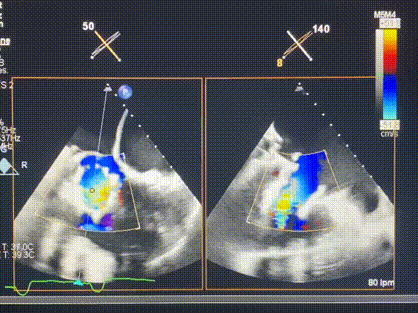

術后超聲顯示僅殘余微量瓣周漏

LuX-Valve Plus經血管三尖瓣置換系統此次“出海”圓滿完成,術后Rodrigo Estévez-Loureiro教授對LuX-Valve Plus經血管三尖瓣置換系統的器械性能和治療效果大為稱贊,認為LuX-Valve Plus的手術體驗非常好。術后即刻超聲顯示三尖瓣反流幾乎完全消失,血流動力學改善顯著,患者恢復快。在面對復雜解剖結構、超聲影像質量不佳、有起搏導線干擾時,Lux-Valve Plus也體現了極強的適應性。Thomas Modine教授和Anson Cheung教授也肯定了LuX-Valve Plus術中操作的便捷性,認為LuX-Valve Plus容錯率高,對術中影像的依賴較小,后期希望可以更多的應用LuX-Valve Plus三尖瓣置換系統于臨床實踐,讓更多的三尖瓣重度反流患者盡早獲益,改善預后。